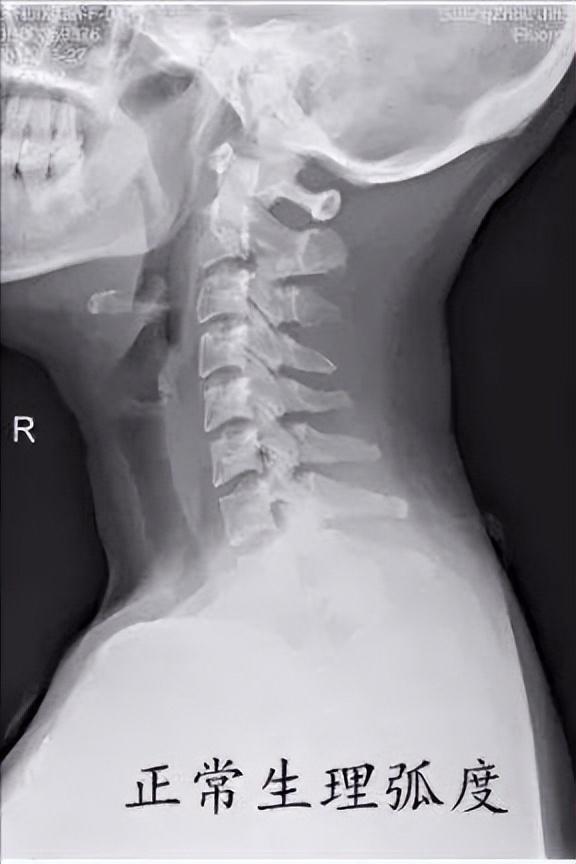

现在的年轻人大多长时间低头看电脑或则低头看手机,经常出现颈部疼痛、落枕、头晕头痛等不适,就诊拍片子经常能看到如下这些情况

这些片子提示你的颈椎的生理弯曲已经消失,甚至出现了反弓。为啥会出现这种情况呢?

首先我们先来了解我们颈椎正常生理情况。正常的颈椎有一个微微向前的生理弯曲,如下图。它的作用就像个弹簧一样,有效的缓解颈部受到的震荡,而且可以维持姿势的稳定性。